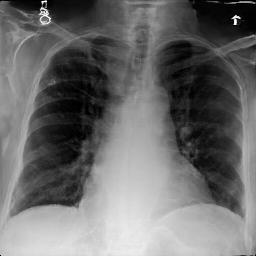

Image Reconstruction. Table 1 shows that the co-training scheme outperforms the \mathcal{E}-training approach in reconstruction accuracy, as indicated by higher PSNR and IW_SSIM scores, highlighting the benefits of joint optimization for enhancing reconstruction quality. The results are further validated by the visual comparison in Fig. 2, where the co-training scheme recovers input images with finer details and higher fidelity. In contrast, the \mathcal{E}-training scheme exhibits noticeable discrepancies when compared to the original images.

Refer to caption

XRX_{R}

Co-training

\mathcal{E}-training

Fig. 2: Reconstruction results. The first row displays the real images XRX_{R}. The last two rows show the reconstructed images X^R\hat{X}_{R} produced by the proposed co-training scheme and the \mathcal{E}-training scheme, respectively.